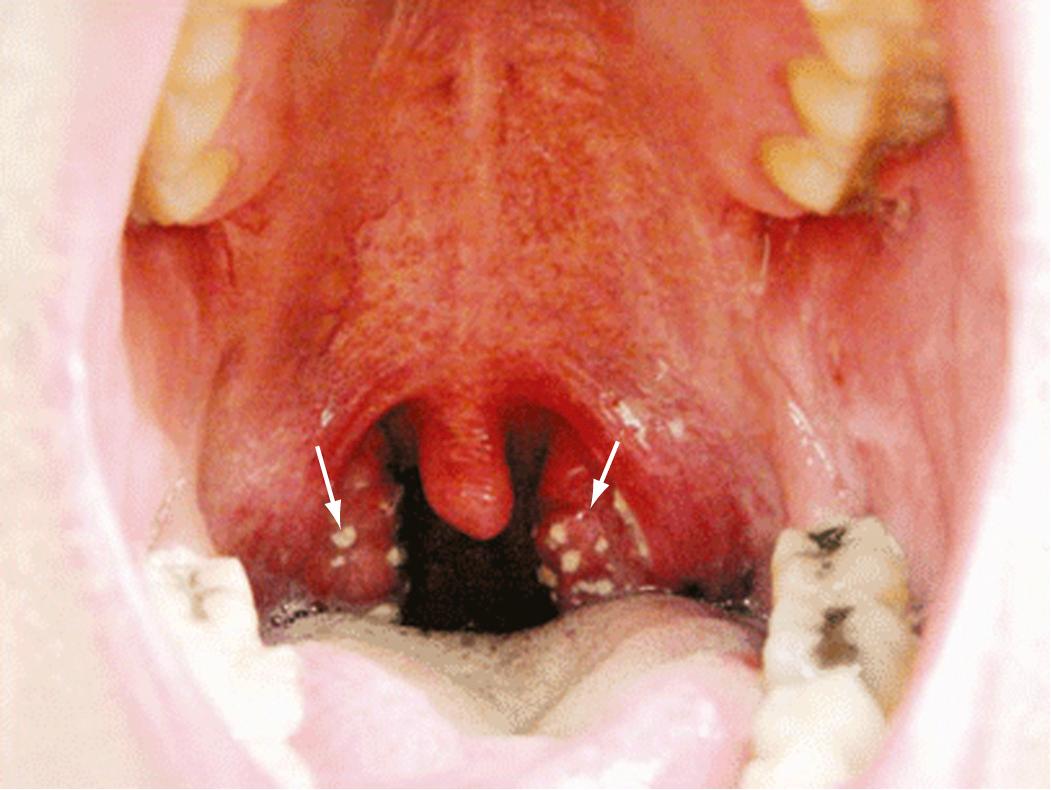

The usual incubation period of streptococcal pharyngitis is 2 to 4 days. The onset of illness is heralded by the rather abrupt onset of sore throat accompanied by malaise, feverishness, and headache. Nausea, vomiting, and abdominal pain are common in children. Prominent physical findings include redness, edema, and lymphoid hyperplasia of the posterior portion of the pharynx; enlarged, hyperemic tonsils; patchy discrete tonsillopharyngeal exudates ( Fig. 197.3 ); enlarged, tender lymph nodes at the angles of the mandibles; and a temperature of 38.3°C (101°F) or higher. In the absence of these symptoms and signs, simple coryza, hoarseness, cough, or conjunctivitis does not suggest the presence of streptococcal infection. Laboratory findings include a positive throat culture for β-hemolytic streptococci and a total white blood cell (WBC) count usually exceeding 12,000/mm, with increased numbers of PMNs. The test for C-reactive protein is usually positive.

FIG. 197.3, Streptococcal tonsillopharyngitis.